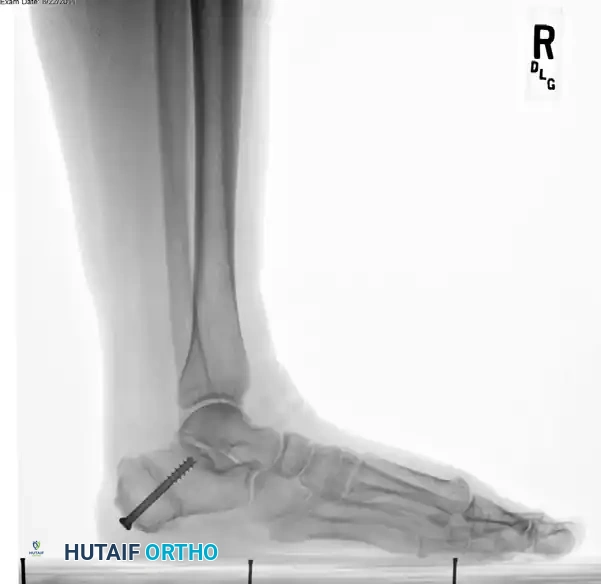

5. Fixation

- Once the 10 mm medial translation is achieved and held provisionally with a smooth Steinmann pin, prepare for definitive fixation.

- Secure the osteotomy with a single, large-diameter (6.5 mm to 7.3 mm) cannulated, self-tapping, partially threaded cancellous screw.

- Trajectory: Insert the guidewire from the posteromedial and inferior aspect of the calcaneal tuberosity, directing it toward the anterolateral and superior aspect of the anterior calcaneal process (aiming toward the sinus tarsi).

- Ensure rigid compression across the osteotomy site.

Surgical Warning: To ensure rigid fixation and prevent iatrogenic arthritis, strictly avoid inserting the screw into the posterior facet of the subtalar joint. Intraoperative fluoroscopy (Broden's views and lateral views) is essential to confirm extra-articular hardware placement.